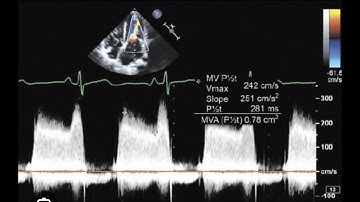

How to...Measure MVA using PHT or Deceleration Time